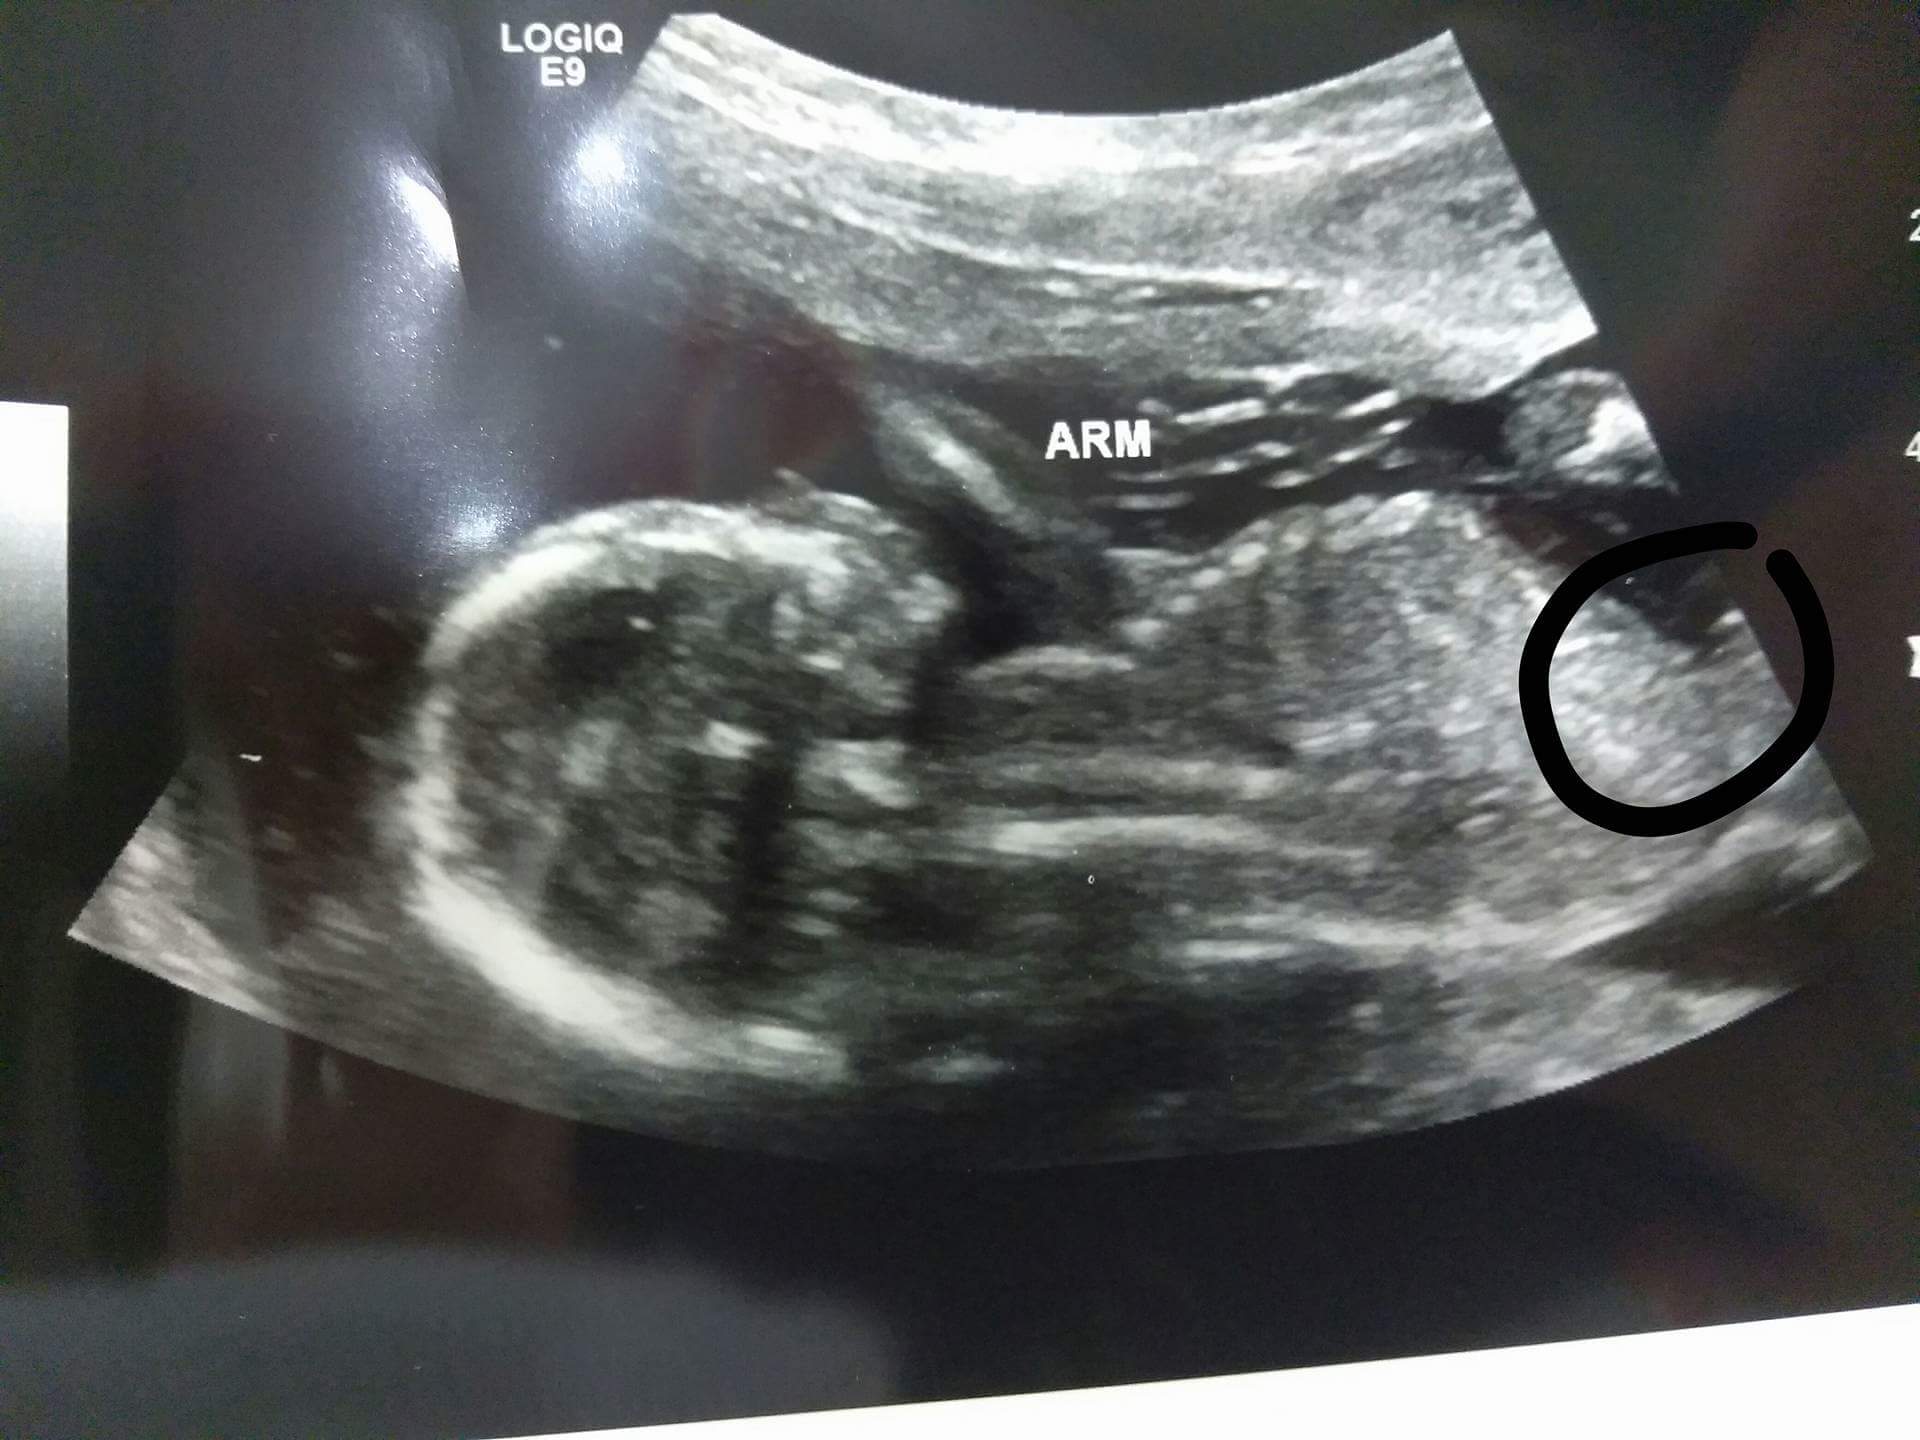

I think it's a girl because I don't see any boy parts, the skull also looks like my previous girls. Any guesses?

At 17 weeks, you need a potty shot to see gender. Do you have one?

Looks like a girl to me x